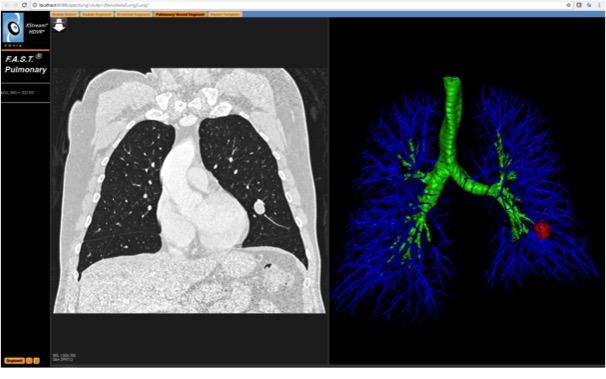

Their are 2 F.A.S.T.Pulmonary example

applications (shown below).

The first one demonstrates a more typical UI expereince for

Advanced Visualization application. The Clinical use case for this app

would be to segment out multiple structures from a chest CT scan to

answer a number of clinical questions about low dose lung nodule

screening. This app will demonstrate a number of rendering techniques:

The first one demonstrates a more typical UI expereince for an Advanced Visualization application. The Clinical use case for this app would be to segment out multiple structures from a chest CT scan to answer a number of clinical questions about low dose lung nodule screening. This app will demonstrate a number of rendering techniques:

as well as how F.A.S.T. Interactive Segmentation can used to segment out :